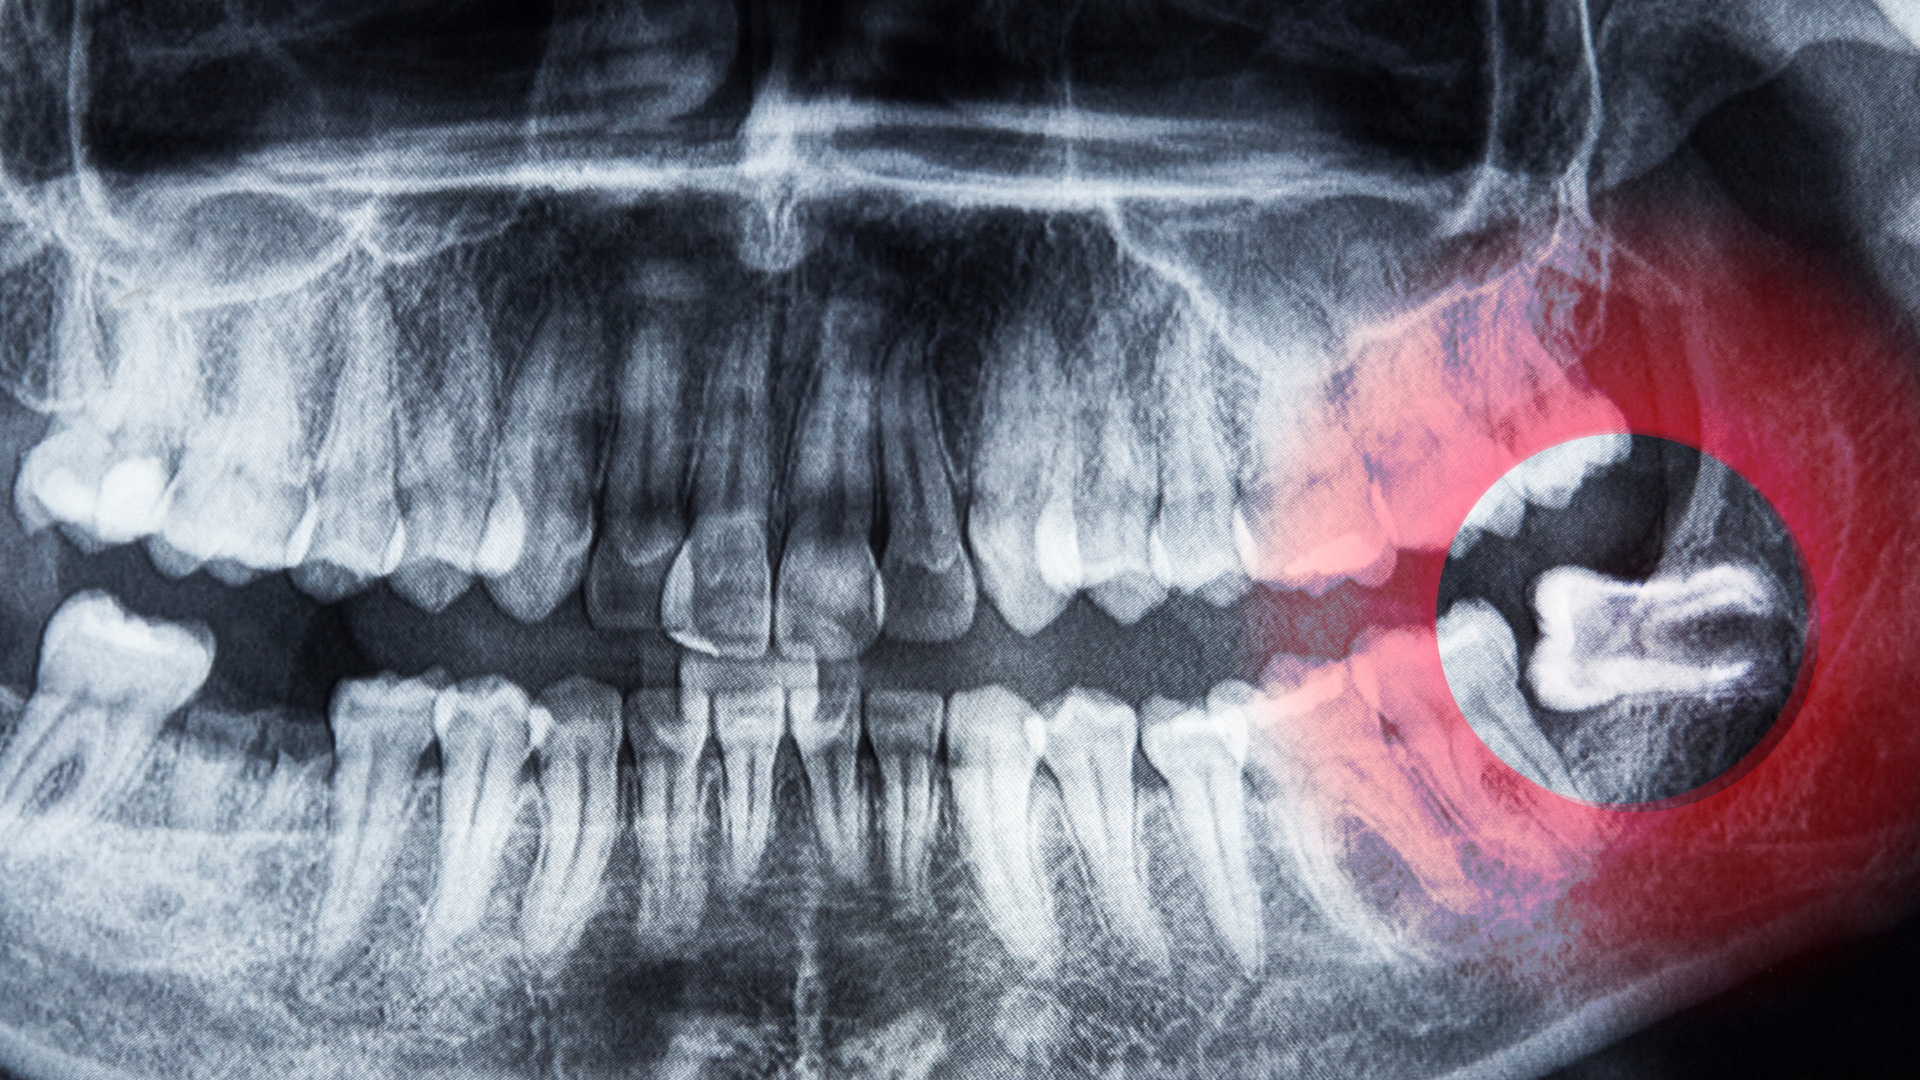

Răng khôn mọc ngang 90 độ là tình trạng răng khôn mọc lệch ngang, tạo góc gần như vuông so với trục thẳng đứng của các răng mọc bình thường. Thay vì hướng lên trên để trồi ra khỏi nướu đúng vị trí, thân răng nằm kẹt trong xương hàm hoặc lợi, tựa sát và chèn ép trực tiếp vào mặt bên của răng số 7 phía trước. Vì hướng mọc hoàn toàn sai lệch, chiếc răng này không thể trồi lên đúng vị trí nhai và không có chức năng thực sự trong bộ răng. Đây là một trong những dạng mọc lệch nặng nhất trong số các trường hợp bất thường về răng khôn.

Tuy nhiên, đáng lưu ý là trong nhiều trường hợp người bệnh hoàn toàn không có triệu chứng rõ ràng và chỉ phát hiện tình trạng răng khôn mọc ngang qua phim X-quang khi đi khám định kỳ. Đây chính là lý do khám răng định kỳ đóng vai trò quan trọng trong phát hiện sớm.

Khi răng khôn mọc ngang 90 độ nằm ở vị trí sâu trong xương hàm và gần ống thần kinh hàm dưới, việc chèn ép kéo dài hoặc can thiệp điều trị muộn có thể ảnh hưởng đến dây thần kinh cảm giác. Người bệnh có thể trải qua tê môi dưới, tê vùng cằm hoặc cảm giác châm chích dai dẳng ở những vùng này. Tỷ lệ xảy ra biến chứng này không cao, nhưng do mức độ ảnh hưởng đến chất lượng cuộc sống khá rõ rệt, người bệnh cần được tư vấn thăm khám chuyên khoa để đánh giá chính xác qua phim X-quang trước khi quyết định bất kỳ phương án điều trị nào.

Tuy nhiên, quyết định cuối cùng luôn cần dựa trên đánh giá toàn diện bao gồm hình ảnh phim X-quang chi tiết, tình trạng viêm nhiễm hiện tại và đặc biệt là vị trí của chân răng so với đường đi của dây thần kinh hàm dưới. Mỗi người bệnh có cấu trúc giải phẫu khác nhau, vì vậy chỉ bác sĩ răng hàm mặt được đào tạo chuyên sâu mới có thể tư vấn phương án phù hợp nhất.